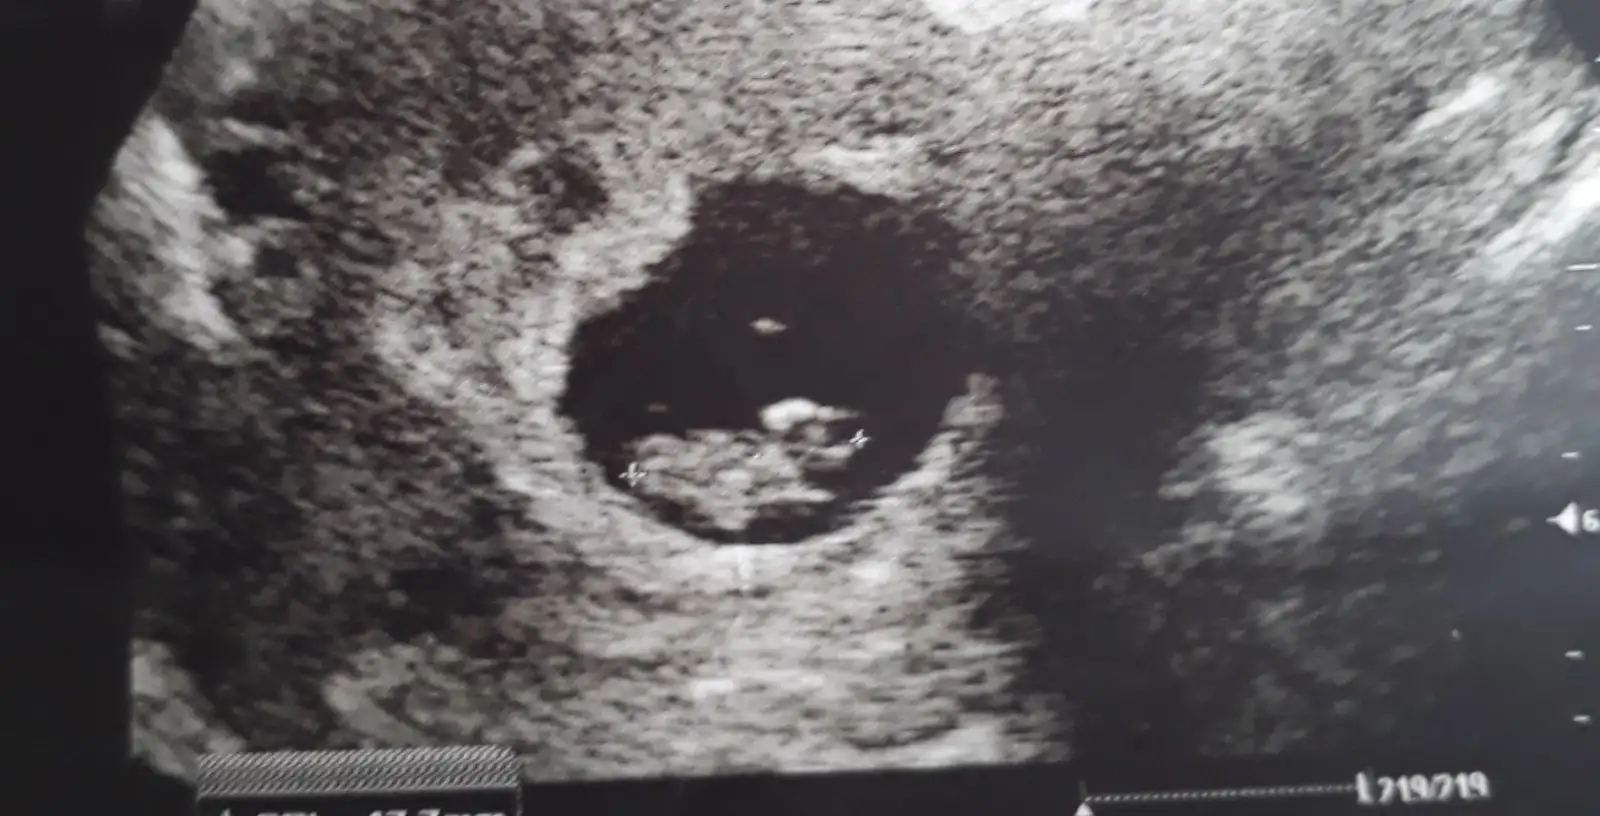

Canim daha erken bilyosun bu bir tahmin cnm kesedeki konumu...[QUOTE ="DenizZkabugu, post: 57860190, member: 865340"]Gmz1292 Merhaba canım 8+2 yim bende pek belli olmuyo ama rica etsem banada bakarmisin

Teşekkür ederim fikrini alayım dedim bende kesedeki konumuna göre kıza benzettim ilerleyen haftalarda danisirim tekrar canım çok saol[/QUOTE]Canim daha erken bilyosun bu bir tahmin cnm kesedeki konumu...